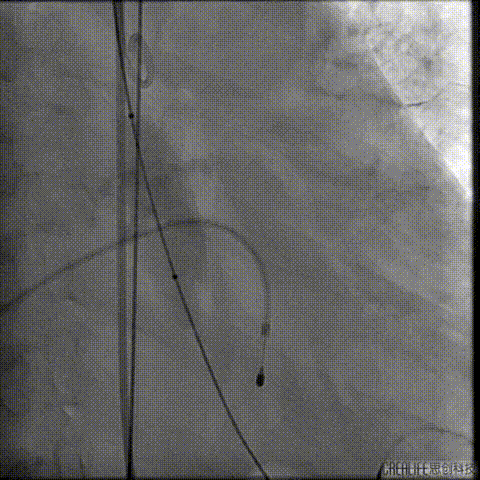

经桡冠脉保护

置入Venus-A32号瓣膜并释放

复查造影

撤出冠脉保护

再次复查造影